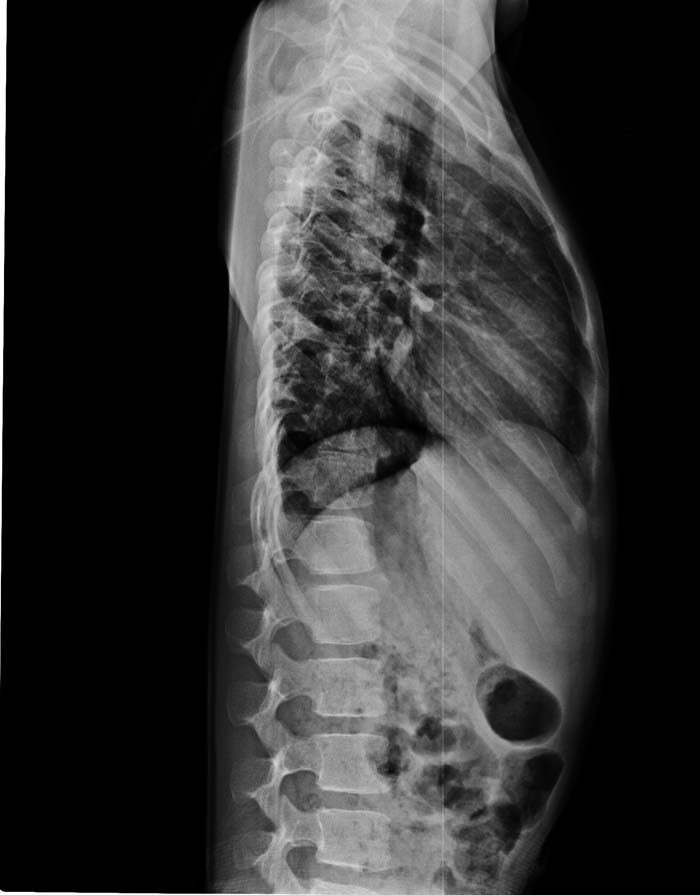

以下是引用zsl6918在2009-10-17 18:51:00的发言:[br]融椎畸形

以下是引用zy_zj在2009-10-17 19:21:00的发言:[br]胸椎8,9椎体融合畸形,伴序列s形弯曲,颈椎稍侧弯,曲度反向。

以下是引用余辉在2009-10-18 10:20:00的发言:[br]支持椎体隔合畸形,肋骨亦有融合,局部椎体密度较低,棘突影像缺如,不排除合并椎体裂,建议ct检查